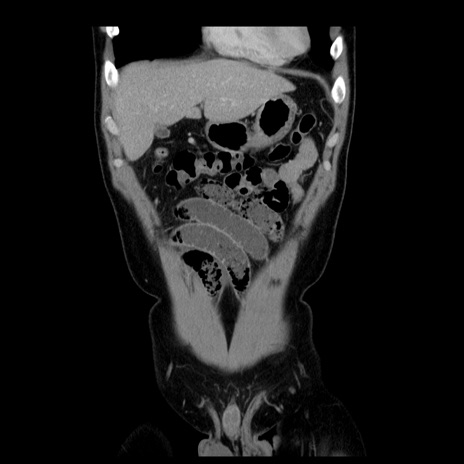

横断像

【症例】30歳代男性

【主訴】腹痛、嘔吐

【現病歴】昨晩から突然の腹痛あり、その後嘔吐、軟便も出現。腹痛が改善しないため救急搬送となる。2日前にしめ鯖の食事歴あり。

【身体所見】意識清明、苦悶様、BP 135/90mmHg、BT 35.7℃、腹部:平坦、やや硬、心窩部〜臍部に自発痛、圧痛あり、筋性防御+、反跳痛-

【データ】WBC 8100、CRP 0.57